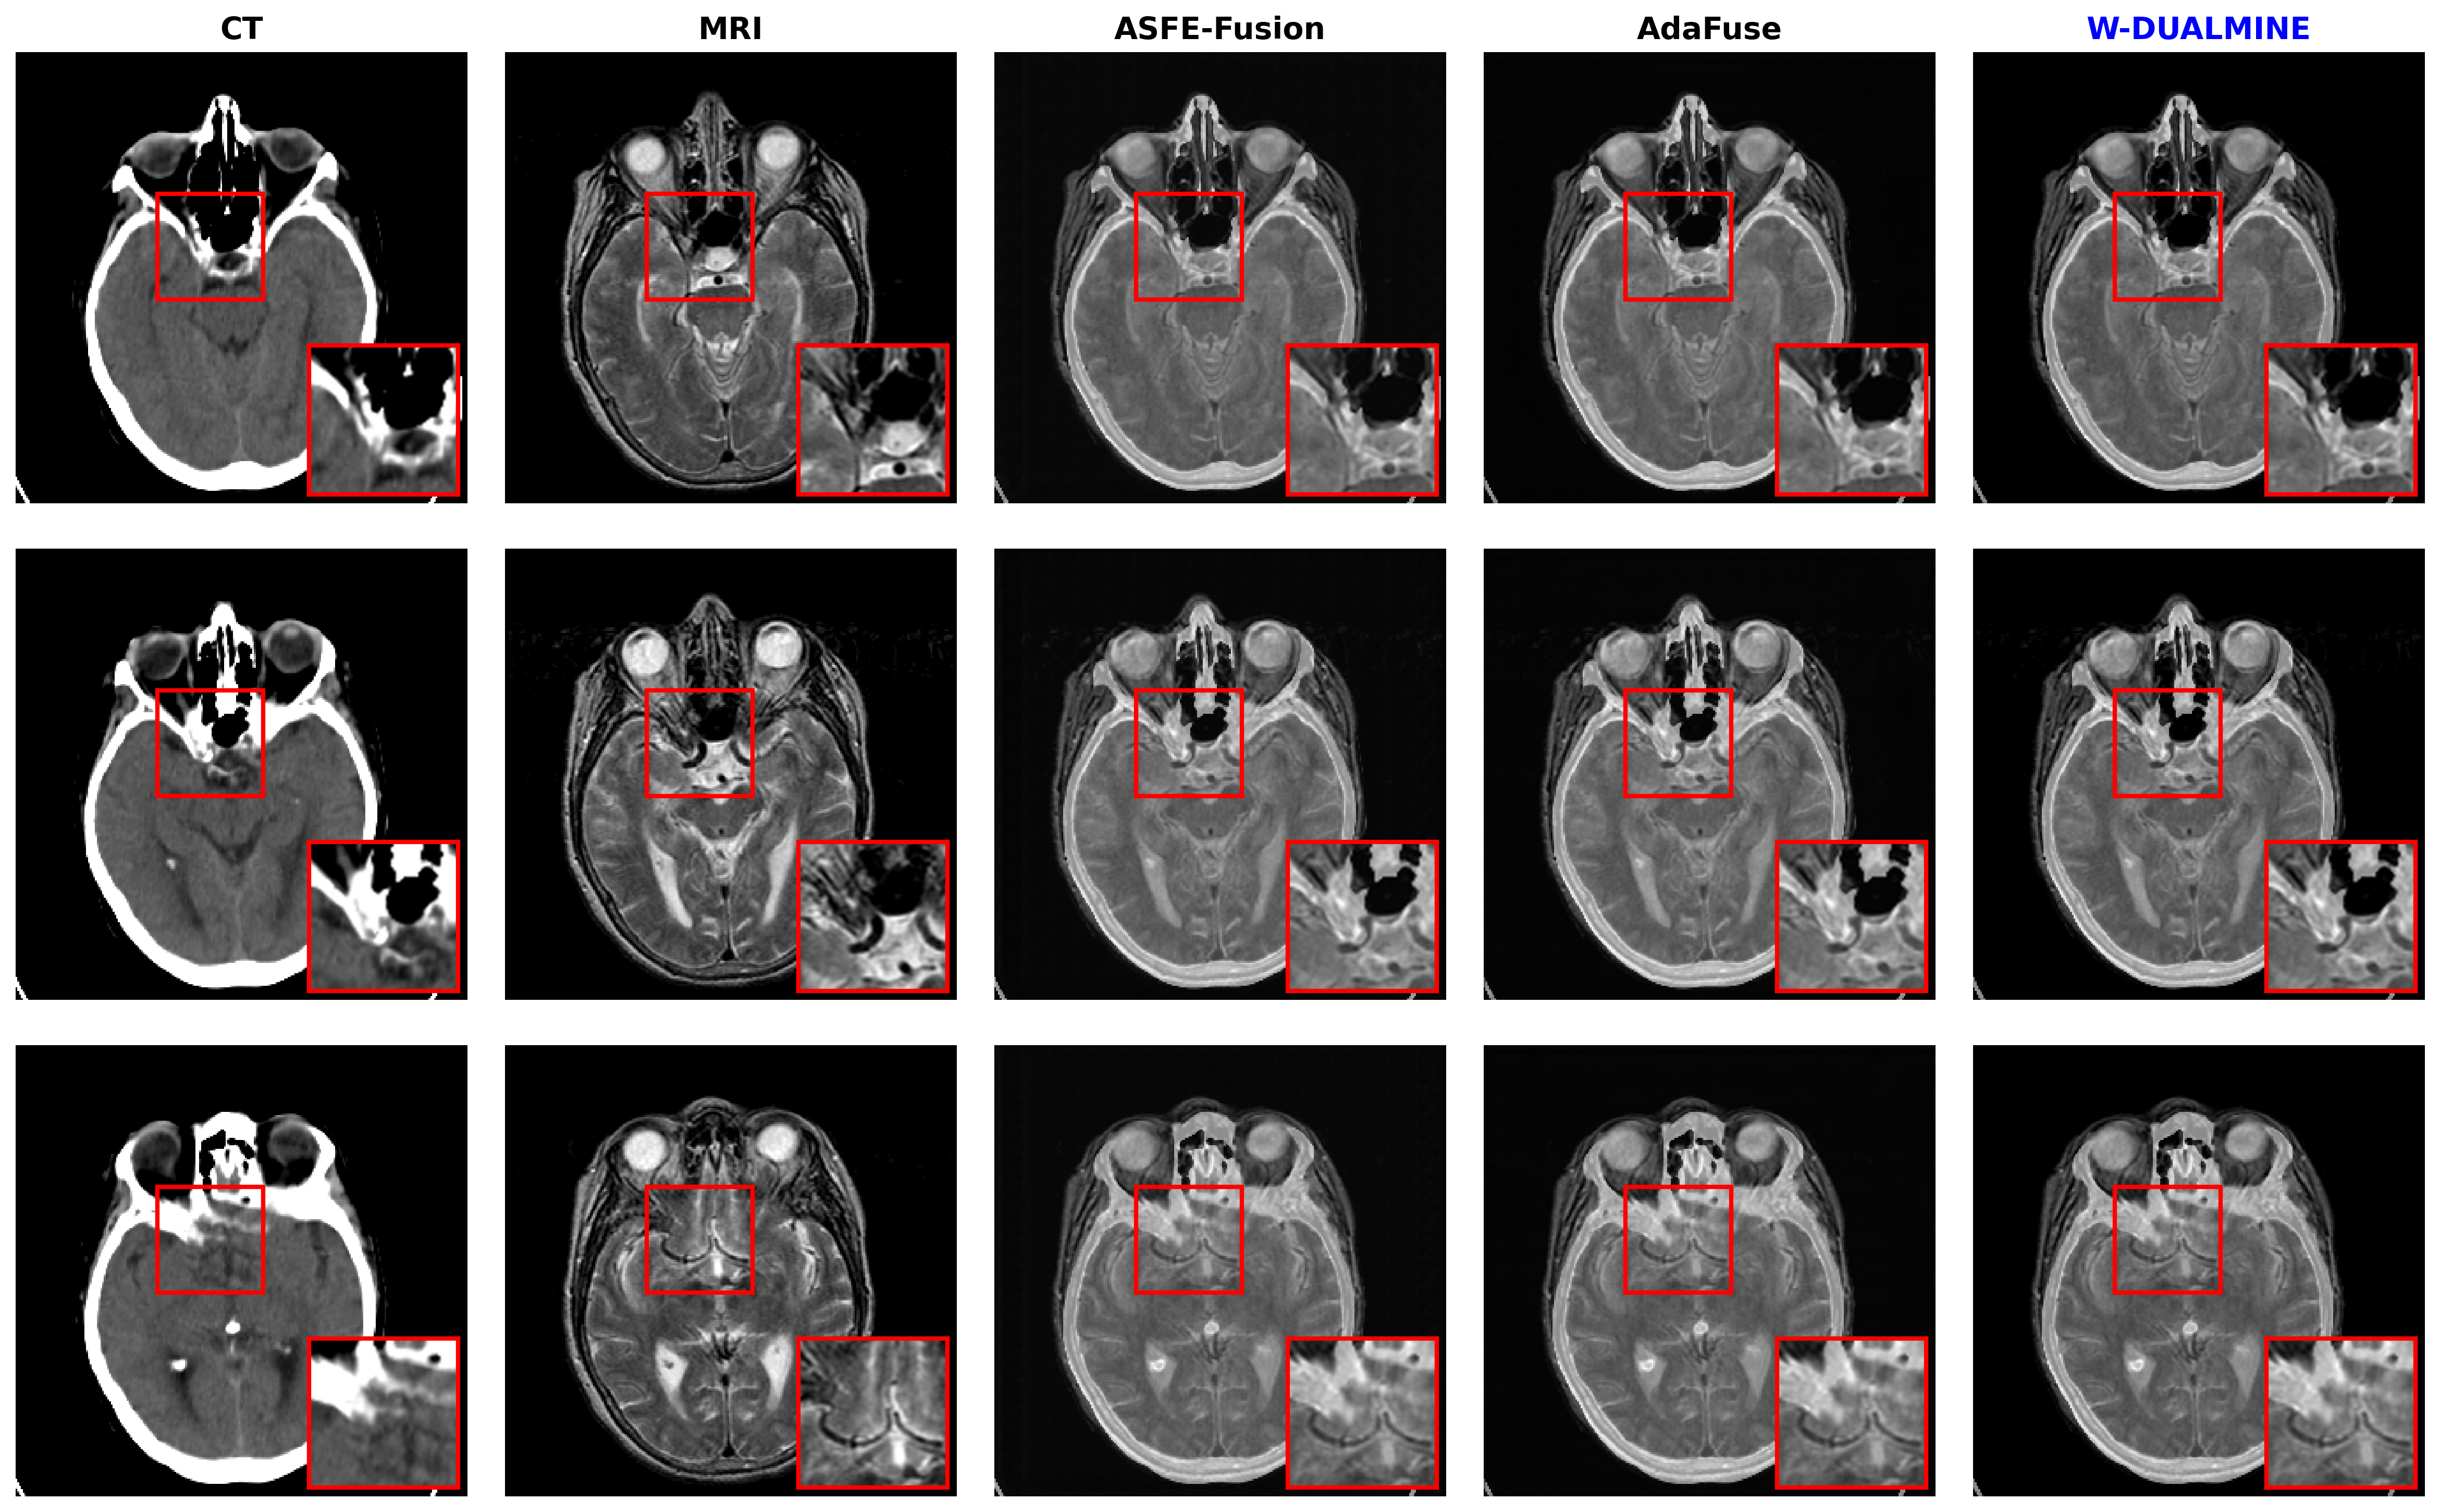

5.3.1 Results on CT–MRI Dataset

The CT–MRI task involves integrating high-contrast bone structures (CT) with soft-tissue details (MRI). The quantitative results are presented in Table 1.

Refer to caption

Figure 3: Qualitative comparison on the CT–MRI fusion task. From left to right: CT image, MRI image, ASFE-Fusion, AdaFuse, and W-DUALMINE. Red boxes highlight regions of interest for detailed comparison. The proposed method preserves sharp CT structures while maintaining MRI soft-tissue contrast.

As shown in Figs. 35, W-DUALMINE produces visually superior fusion results across all modalities. The proposed method achieves better structural clarity and functional consistency than ASFE-Fusion and AdaFuse, particularly in highlighted regions.